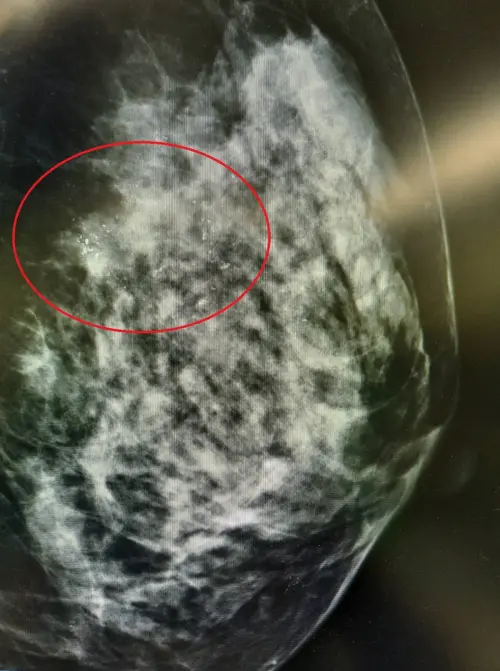

53歲張小姐日前接受乳房攝影檢查,發現右側有瀰漫性微小鈣化點,進一步接受切片後,確診為乳管原位癌,病灶尚未轉移,經與醫師討論後,她選擇進行一次性乳房切除與重建手術,僅開刀一次,即可完成所有治療計畫,術後恢復良好,2日後平安出院。

▲張小姐乳房攝影檢查發現有瀰漫性微小鈣化點。(圖/台北慈願提供) 張健輝於2024年3月取得此專科資格,他指出,單一醫師手術中即時調整切除範圍及重建計畫,更能確保兩側乳房對稱、外觀自然,也可避免病人反覆面臨手術風險,大幅提升安全性。